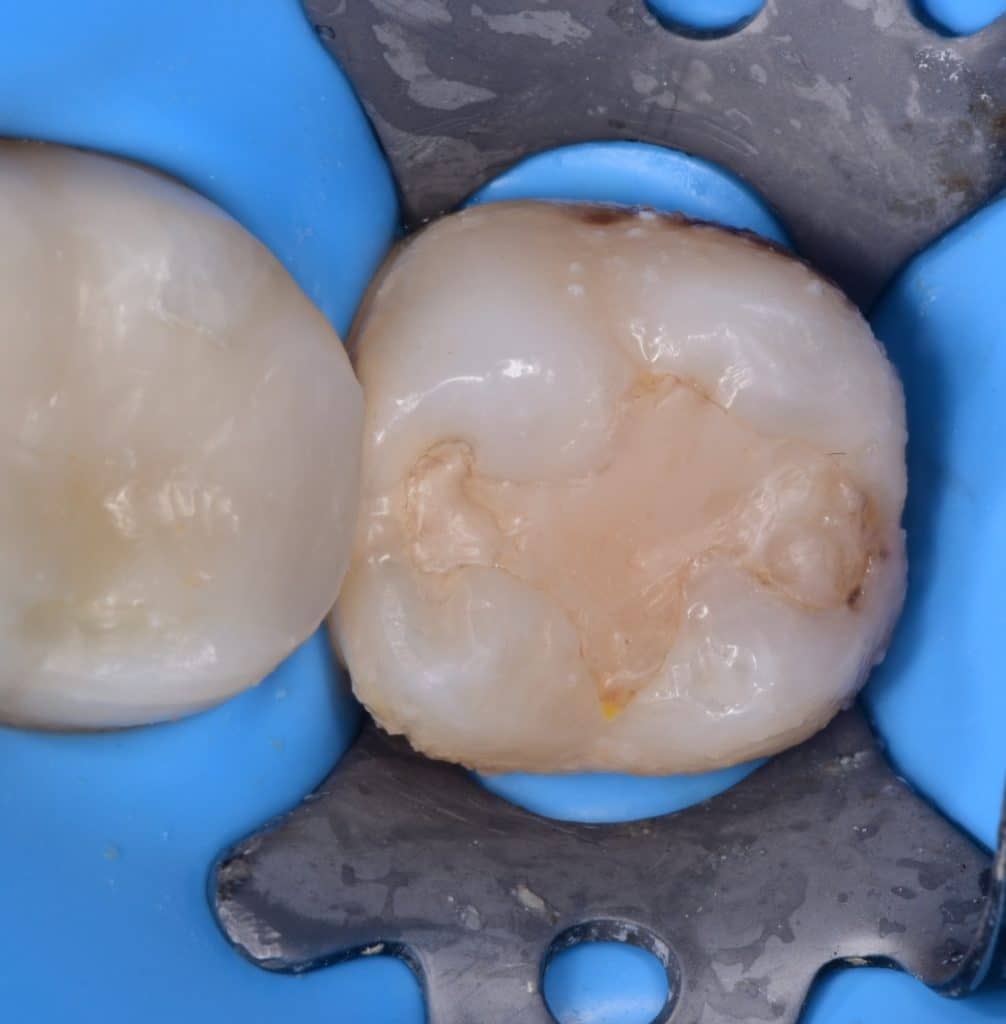

Initial situation